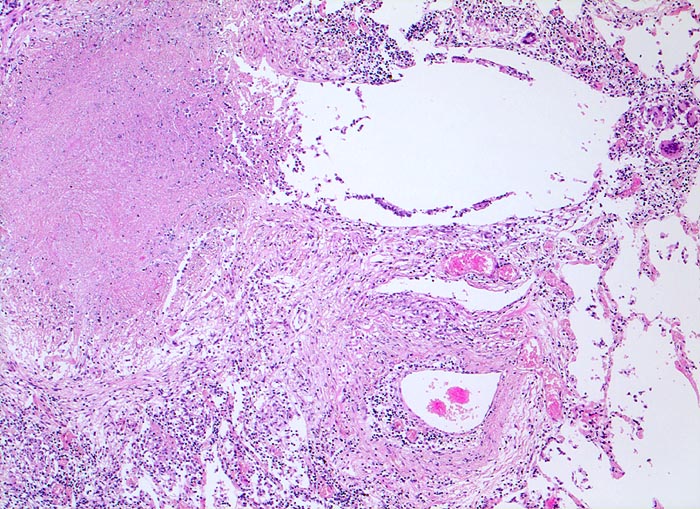

Das morphologische Bild ist äusserst variabel. Je nach Abwehrlage, Art und Geschwindigkeit der Ausbreitung entstehen unterschiedlich grosse, teils geschichtete Herde mit unterschiedlichem Grad an Epitheloidzellreaktion, zentraler Nekrose bzw. Vernarbung. Rein produktive Granulome ohne Nekrosen sind Zeichen guter Abwehrlage. Der Begriff Verkäsung bezieht sich auf den makroskopischen Aspekt von Nekrosen, der an Frischkäse erinnert. Exsudative nekrotisierende Granulome entstehen bevorzugt bei schlechter Abwehrlage. In späteren Stadien der Lungentuberkulose unterscheidet man produktive Phthisen mit azinös nodösen Gruppen von bronchogen entstandenen gering verkäsenden Streuherden (Präparat), zirrhotische Phthisen mit gering verkäsenden stark vernarbenden Herden und exsudative Phthisen bei schlechter Abwehrlage. Bei letzterer steht die Verkäsung im Vordergrund. Die bakterienreichen Herde entstehen teils hämatogen, teils bronchogen. Verkäsende Herde sind Ausgangspunkt für die Kavernenbildung. Kavernen stellen die wichtigste Quelle für die bronchogene Streuung dar.

• Tuberkulöse Herde ausgehend von vollständig oder partiell entzündlich zerstörten Bronchiolen in unmittelbarer Nachbarschaft von Arterien.

• Granulome mit zentraler käsiger Nekrose mit Kerntrümmern umgeben von einem Epitheloidzellwall und einem äusseren blauen Saum von Lymphozyten.

• Schlanke spindelige Epitheloidzellen und einzelne Riesenzellen vom Langhanstyp mit peripher hufeisenförmig angeordneten Kernen.